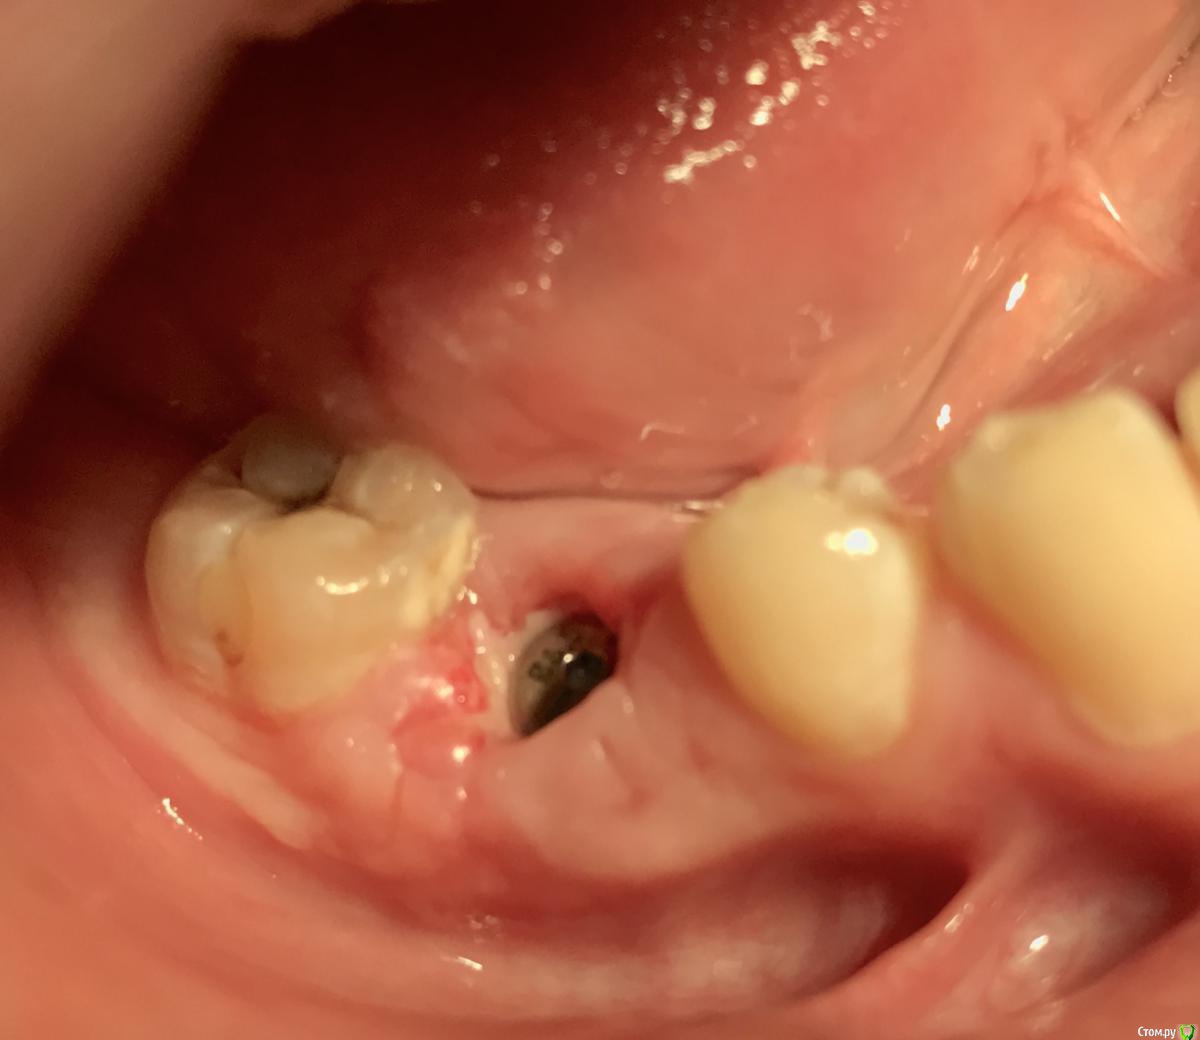

колесников Опубликовано 8 мая, 2017 Поделиться Опубликовано 8 мая, 2017 Немного модифицировал методику Палачи (образование прикреплённой кератинизированой десны междуимплантами,путём выделения и ротирования лоскута с неба). На в/ч у нас обширное поле деятельности со значительными полями кератинизированой слизистой на небе и бугре,что позволяет выделять полосочки не только для пластики в области имплантов,но и для консервации лунки. Можно выделить бугор на питательной ножке и перекинуть его на место 7го. Вариант отсутствует 6ой,присутствует 7ой - выделяем бугор и ведём по маргинальному краю неба у 7го расщепленным разрезом. Длинна может быть значительная,главное свободный конец зафиксировать не в стык а под расщеплённый лоскут принимающего ложа. Одним словом на в/ч с выделением просто. Как быть на н/ч? Обычно только свободный трансплантат с того же неба. Единственный вариант когда можно обойтись местными тканями:отсутствуют нижние 7,8,необходима консервация либо дополнительный объём кератинизированой десны у 7ки. Выделяется с дистального края лунки расщепленная кератинизрованая полоска и далее ведётся по язычному краю лунки . Получаем такую узкую ,но довольно длинную змейку,которую можем зафиксировать медиально, расположив по вестибулярному краю лунки ,либо по язычному ,либо завернуть спиралью. Можно ретромолярно выделить деэпителизированый трансплантат и на подобной змейке перенести его вестибулярно к 7ке. Фото неважные,изначально я не придал значения тому что делаю,позднее результат порадовал объёмом и скоростью регенерации. 1 Ссылка на комментарий

колесников Опубликовано 9 мая, 2017 Автор Поделиться Опубликовано 9 мая, 2017 Да,"приберечь " это про низ. Бугор берётся расщеплённый,не полностью, хорошо регенерирует . Через 4 недели можно брать снова. Травма у нас местно есть в любом случае,кератинизированая расщеплённая десна регенерирует очень хорошо и малоболезненно. Как пример фото разместил :в первом случае со "змейки " я снял швы через неделю и простился,во втором ,где свободный лоскут,остатки его убрал через 3 недели и ещё неделя наблюдений.На фото расщеплённый бугор. На последнем -с выделенным сст. Ссылка на комментарий